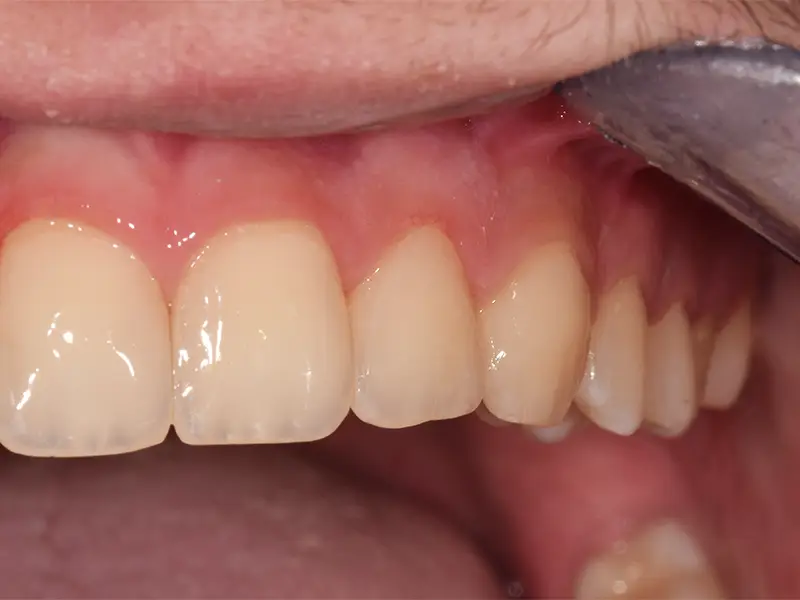

L’odontoiatria conservativa ha l’obiettivo di curare i denti colpiti da carie o lesioni senza ricorrere all’estrazione, ripristinando forma, funzione ed estetica. È un approccio moderno, poco invasivo e focalizzato sulla preservazione del tessuto dentale sano.

Presso lo Studio Dentistico Genzano a Prato, trattiamo le carie e le fratture con tecniche adesive avanzate, materiali estetici e attenzione al dettaglio.

Dopo la diagnosi e la rimozione del tessuto danneggiato, il dente viene ricostruito con materiali compositi estetici di ultima generazione. Utilizziamo la diga di gomma per isolare il campo operatorio e garantire una sigillatura ottimale.

Il trattamento è completamente indolore e, una volta completato, il dente recupera pienamente solidità, funzione masticatoria e integrità strutturale. Il restauro sarà inoltre del tutto invisibile!